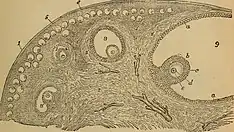

Ovarian stem cells are oocytes formed in ovarian follicle before birth in female mammals. They do not form post-natally, and are depleted throughout reproductive life.[1] In humans it is estimated that 500,000–1,000,000 primordial follicles are present at birth, decreasing rapidly with age until roughly age 51 when ovulation stops, resulting in menopause.[2] The origin of these oocytes remains under discussion. The publication of a study in 2004 proposing germ cell renewal in adult mice sparked a debate on the possibility of stem cells in the postnatal ovary.[2] An increasing number of studies suggest that stem cells exist within the mammalian ovary and can be manipulated in vitro to produce oocytes, but whether such ovarian stem cells have the potential to differentiate into oocytes remains uncertain.[1]